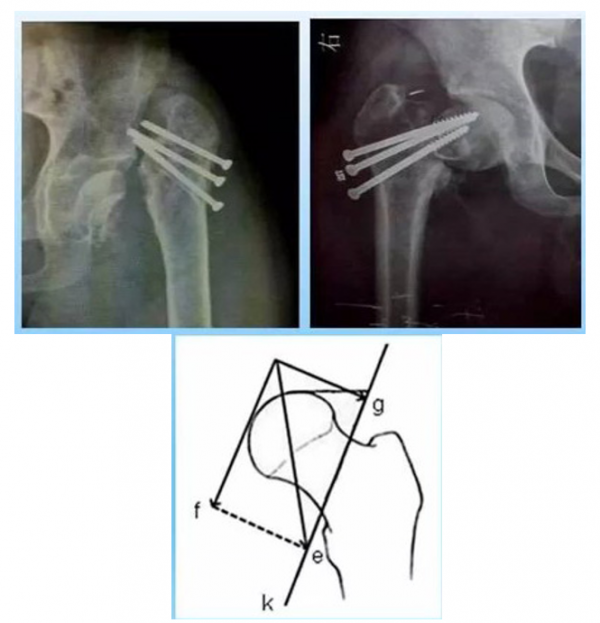

1. 三枚空心螺钉内固定

多用于新鲜青壮年股骨颈骨折;三角形平行螺钉抗拔出及抗剪切能力较弱;“正/倒三角”空心螺钉对于剪切型股骨颈骨折均存在较高失败率。

原因:螺钉的角度稳定性较差,不能对抗此型骨折负重时所产生的强大剪切力(图中f为螺钉所受剪切力,e为负重的应力)。